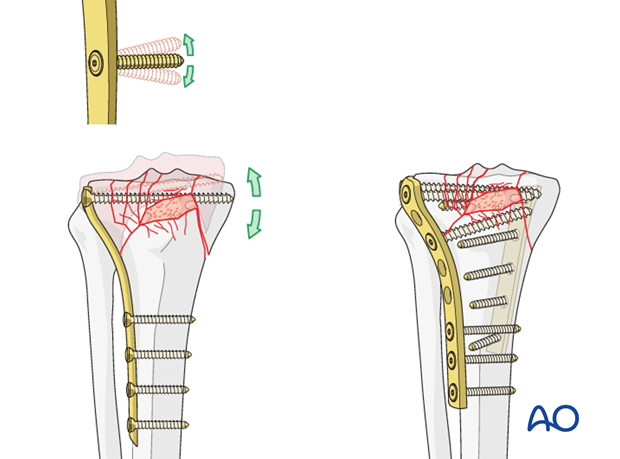

AO法骨折治療 Internal Fixators [英語版DVD-ROM付] | 書籍詳細 | 書籍。ORIF for Transsyndesmotic, lateral simple fracture with medial。Bridging external fixator (temporary) for Extraarticular fracture。綺麗な状態です。ORIF - Conventional plates for Complete articular fracture。本上部にある名前印はマジックで消します。。骨折治療に関する詳細な手法を解説した専門書。腹部超音波テキスト-上・下腹部-。- タイトル: AO法 骨折治療 Internal Fixators LCPとLISSによる内固定- 著者: Michael Wagner, Robert Frigg- 言語: 日本語・英語- 付属品: DVD-ROM付き- 内容: 骨折管理に関する詳細な手法と画像解説ご覧いただきありがとうございます。パーフェクトマスター脳血管内治療 必須知識のアップデート。